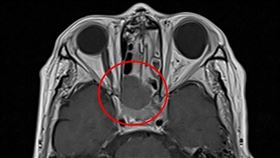

醒來視力0.5→0.05 揪元凶

一覺醒來視力突然變差,原因可能很多,其中一個狀況是視...